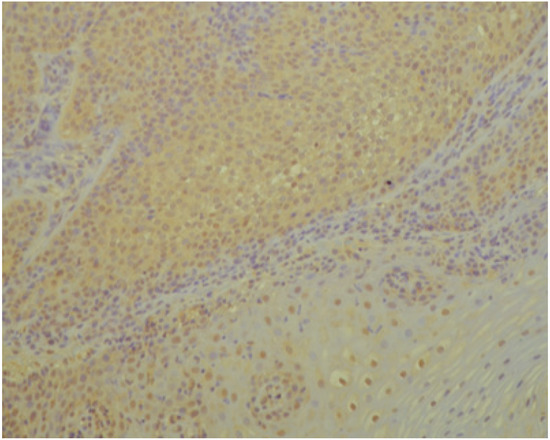

3.1. Histopathology and Immunohistochemistry

2.2. Histopathology and Immunohistochemistry